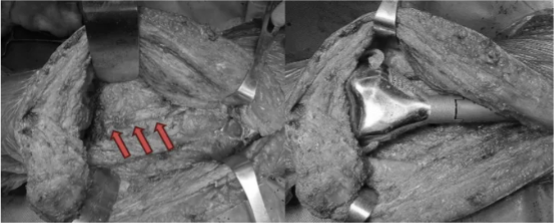

手术由第一人民医院“金手术刀”孙梦熊副主任医生主刀,王崇任主治医师、姜亚飞医师协助。手术历时约4小时,出血300ml。术中肿瘤完整切除,保留了主要的血管和神经,并用假体对膝关节进行了重建。

图示:术中肿瘤完整切除

图示:箭头所示为腘动脉,膝关节半关节假体置换及侧副韧带重建